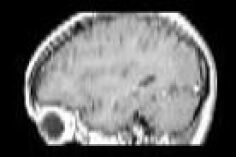

Refer to caption

(a) Captured slice #40 along the saggital plane for Slice sequence of Figure 12a

(b) Reconstructed slice #40 along the saggital plane, given the Slice sequence of Figure 12b

Figure 13: Slice #40 for a human brain along the saggital plane given the Slice sequence of Figure 12b while capture vs after reconstruction